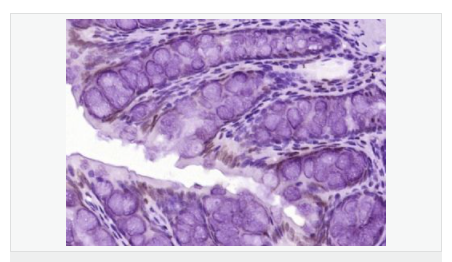

| 產品應用 | WB=1:500-2000 ELISA=1:5000-10000 IHC-P=1:100-500 IHC-F=1:100-500 ICC=1:100-500 IF=1:100-500 (石蠟切片需做抗原修復) not yet tested in other applications. optimal dilutions/concentrations should be determined by the end user. |